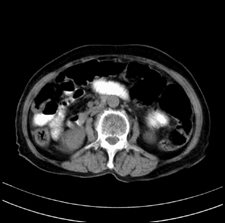

患者,女,75岁。腹痛,体黄5日,膝胸位时腹痛缓解。肝功能明日出来。彩超提示胆总管占位,未见血流信号。心电图提示s-t段改变。患者体质较弱,未能增强。

胆总管结石

胆总管多发结石

胆总管多发结石伴肝内外胆管轻度扩张。

胆总管上段,腔内有软组织密度影 ,ct值36-44hu。大家看有没有胆管癌的可能。

典型胆总管多发结石;增强扫描前后ct值是否发生改变是鉴别结石与占位的依据。